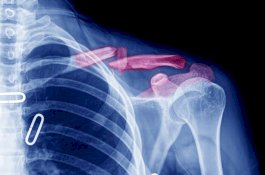

Protes Istri yang Masak Kari Kentang, Suami Dianiaya hingga Tulang Bahu Kanan Patah